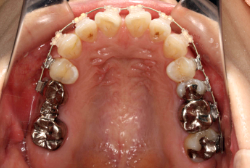

混合歯列期から治療開始した側方拡大による非抜歯症例

「配列の凸凹を治したい」という主訴で来院したケースです。診断の結果、永久歯がすべて生えそろうと、かなり厳しい叢生(歯並びの凸凹のことです)になる可能性が高いと判明しました。原因としては特に上の顎の骨が小さいため、歯を収容する容量不足になっていると診断しました。このケースの場合は、成長発育期に治療開始しますので、顎の骨を土台ごと大きくすることが可能です。

そこで、まず急速拡大装置を使用して上顎骨の拡大を行い、上顎骨の容量が拡大したことを確認後、マルチブラケット装置を使って全体の修正をする、と言う二段階の作戦をとることになりました。

この時期に使う急速拡大装置は、適切な診断に基づいて正しく使用することで確実に骨を大きくすることができます。拡大することで隙間が確保できるので、永久歯の抜歯を避けることができます。

急速拡大装置を1日1回装置の中央にある拡大ネジを、ご自身で回して頂くことで25日間くらいかけて、6mmほど拡大しました。拡大後は、上顎の前歯の隙間が広がっていることがお分かりいただけると思うのですが、土台の骨ごと広がるのでこのような隙間ができます。その後1年半くらいマルチブラケット装置を使用して、全体の修正を行いました。

結局、歯の本数を減らすことなく、すべてご自分の歯を残して正しい配列にすることができました。このケースの場合、2009年10月より拡大と経過観察を行い、2012年3月より1年2ヶ月マルチブラケット装置を装着、2013年5月に治療を終了しました。2段階で行う治療としては短期間で終了しているケースと思います。